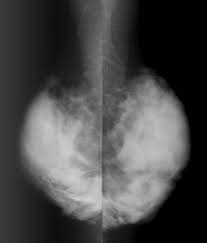

| 검진 항목 | 유방촬영술(Mammography) |

| 유방촬영술(Mammography) | X선 촬영으로 석회화, 종괴 등 확인 | 선별 검사 | 국가검진 기본 항목 |

치밀유방은 유선조직이 많고 지방조직이 적은 구조로, X선상에서 종양과 구분이 어려워 유방촬영만으로는 암을 놓칠 수 있습니다.이 경우 유방초음파를 보완적으로 진행하면 암 발견률을 크게 높일 수 있습니다.

정기적인 유방 촬영(유방촬영술, 맘모그래피)이 생명을 지키는 중요한 열쇠입니다.